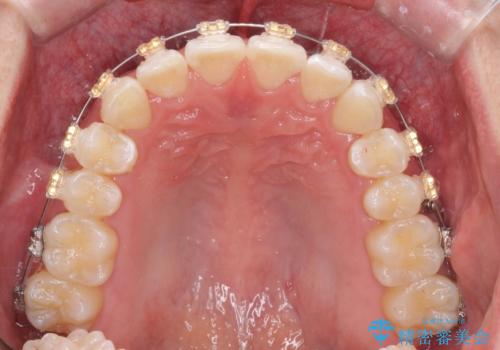

- 20代男性

- ワイヤー

- 10ヶ月

- 取り外しの必要なマウスピース矯正ではなくワイヤー矯正を希望され来院されました。

マウスピース矯正、ワイヤー矯正どちらの方法でも治療は可能ですが、ご要望の通りワイヤー矯正で歯の排列を行っていきます。